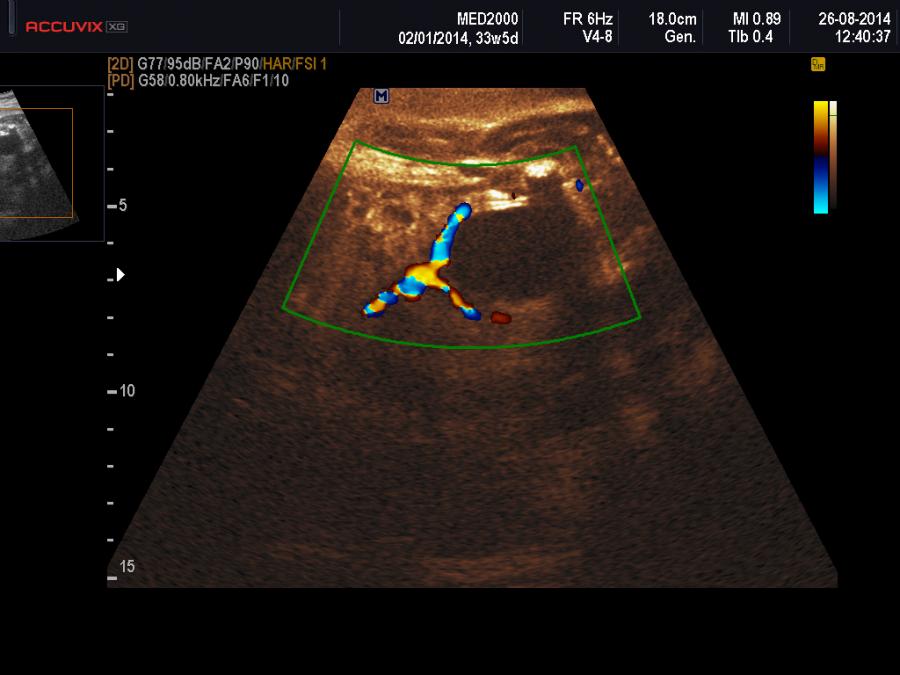

Importanti per la diagnosi sono due elementi: 1) sesso femminile, 2) differenziazione dalla vescica urinaria: tale distinzione è agevole considerando che è possibile evidenziare, con l'ausilio del color-doppler, le due arterie ombelicali che decorrono lateralmente alla vescica.